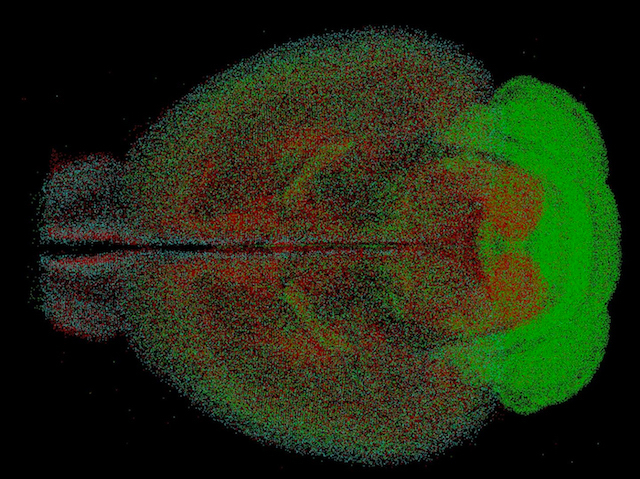

Stop Signals

Trillions of stringy neurons meet up in our brains, passing signals through junctions called synapses. Sometimes, though, these signals need fine-tuning. Inhibitory neurons (highlighted as red, green and blue dots in this mouse brain) connect to synapses to block certain signals, vital to controlling information passing into and out from the brain. Here a technique called qBrain reveals three different types of inhibitory neurons are not spread evenly – the green cells, for example, occur more densely in sensory-motor areas of the brain, which control how we respond to the world. Other qBrain scans reveal that, although females generally have smaller brains, specific areas contain more inhibitory neurons, suggesting more sensitive control of signals associated with reproductive, social and parenting behaviours.